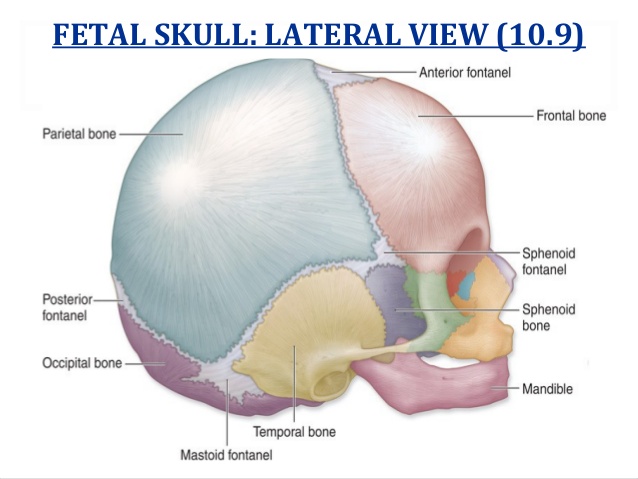

store.toolband.comThe Fetal Skull - Trial Exhibits Inc.

store.toolband.comThe Fetal Skull - Trial Exhibits Inc.

store.toolband.comFetal Skull Positions

store.toolband.comFetal Skull Positions

www.turbosquid.comAnatomi Dan Fisiologi Rangka

www.turbosquid.comAnatomi Dan Fisiologi Rangka

this-ismynursenotes.blogspot.comFetal Skull | Notes.nursium.com

this-ismynursenotes.blogspot.comFetal Skull | Notes.nursium.com

notes.nursium.comskull fetal anterior fontanelle brow bone occiput area occipital corresponds lying front

notes.nursium.comskull fetal anterior fontanelle brow bone occiput area occipital corresponds lying front

store.toolband.comAltay Fetal Skull | Carolina Biological Supply

store.toolband.comAltay Fetal Skull | Carolina Biological Supply

www.carolina.comskull fetal altay carolina

www.carolina.comskull fetal altay carolina